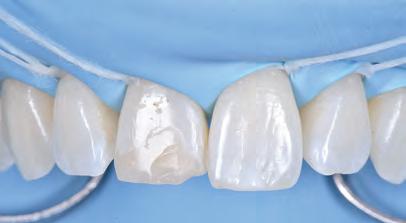

On the day of treatment, following local plexus anaesthesia, UR1 was isolated using a rubber dam, extending the isolation to the first premolars (Figure 4).

Subsequently, the fractured composite reconstruction was removed, a short bevel was performed on the preparation, and the entire surface of UR1 was sandblasted with 27 m aluminium oxide powder (Figure 5).

In order to correct the altered passive eruption, it was decided to recreate the emergence profile of the tooth by accentuating the vestibular bulge and seeking symmetry with the contralateral element. For this purpose, a pre-formed metal matrix was used and was blocked with two wedges. Once the matrix had been adapted, the adhesion procedures were carried out with a three-step etch and

FIGURE 5: Removal of fractured composite restoration.

FIGURE 6: Use of matrix and adhesion with three-step etch&rinse system.

rinse system. Each step was followed by polymerisation with UV light for 40 seconds (Figure 6).

The vestibular emergence profile was recreated with an enamel shade of composite (ESTELITE ASTERIA WE from Tokuyama Dental) (Figure 7). After performing a silicone index of the diagnostic wax-up, the palatine wall was reconstructed by an enamel shade of composite (ESTELITE ASTERIA WE from Tokuyama Dental) (Figure 8).